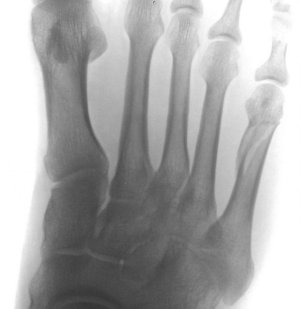

Понятно, а перелом был в каком месте?

Отрывной или Джонса? Если отрывной, то так бывает

Здравствуйте. Мне 38 лет. Перелом 5-ой плюсневой.

Приложенные снимки - на следующий день после случившегося. Сразу в гипс на 5 недель. Ни в травмпункте, ни в поликлинике лечащий врач даже на упоминали операцию.

Только в травмпункте доктор сказал "... с незначительным смещением, поэтому просто гипс на месяц."

Очень хотелось бы узнать Ваше мнение. Есть ли шанс на самостоятельное сращение без оперативного вмешательства.